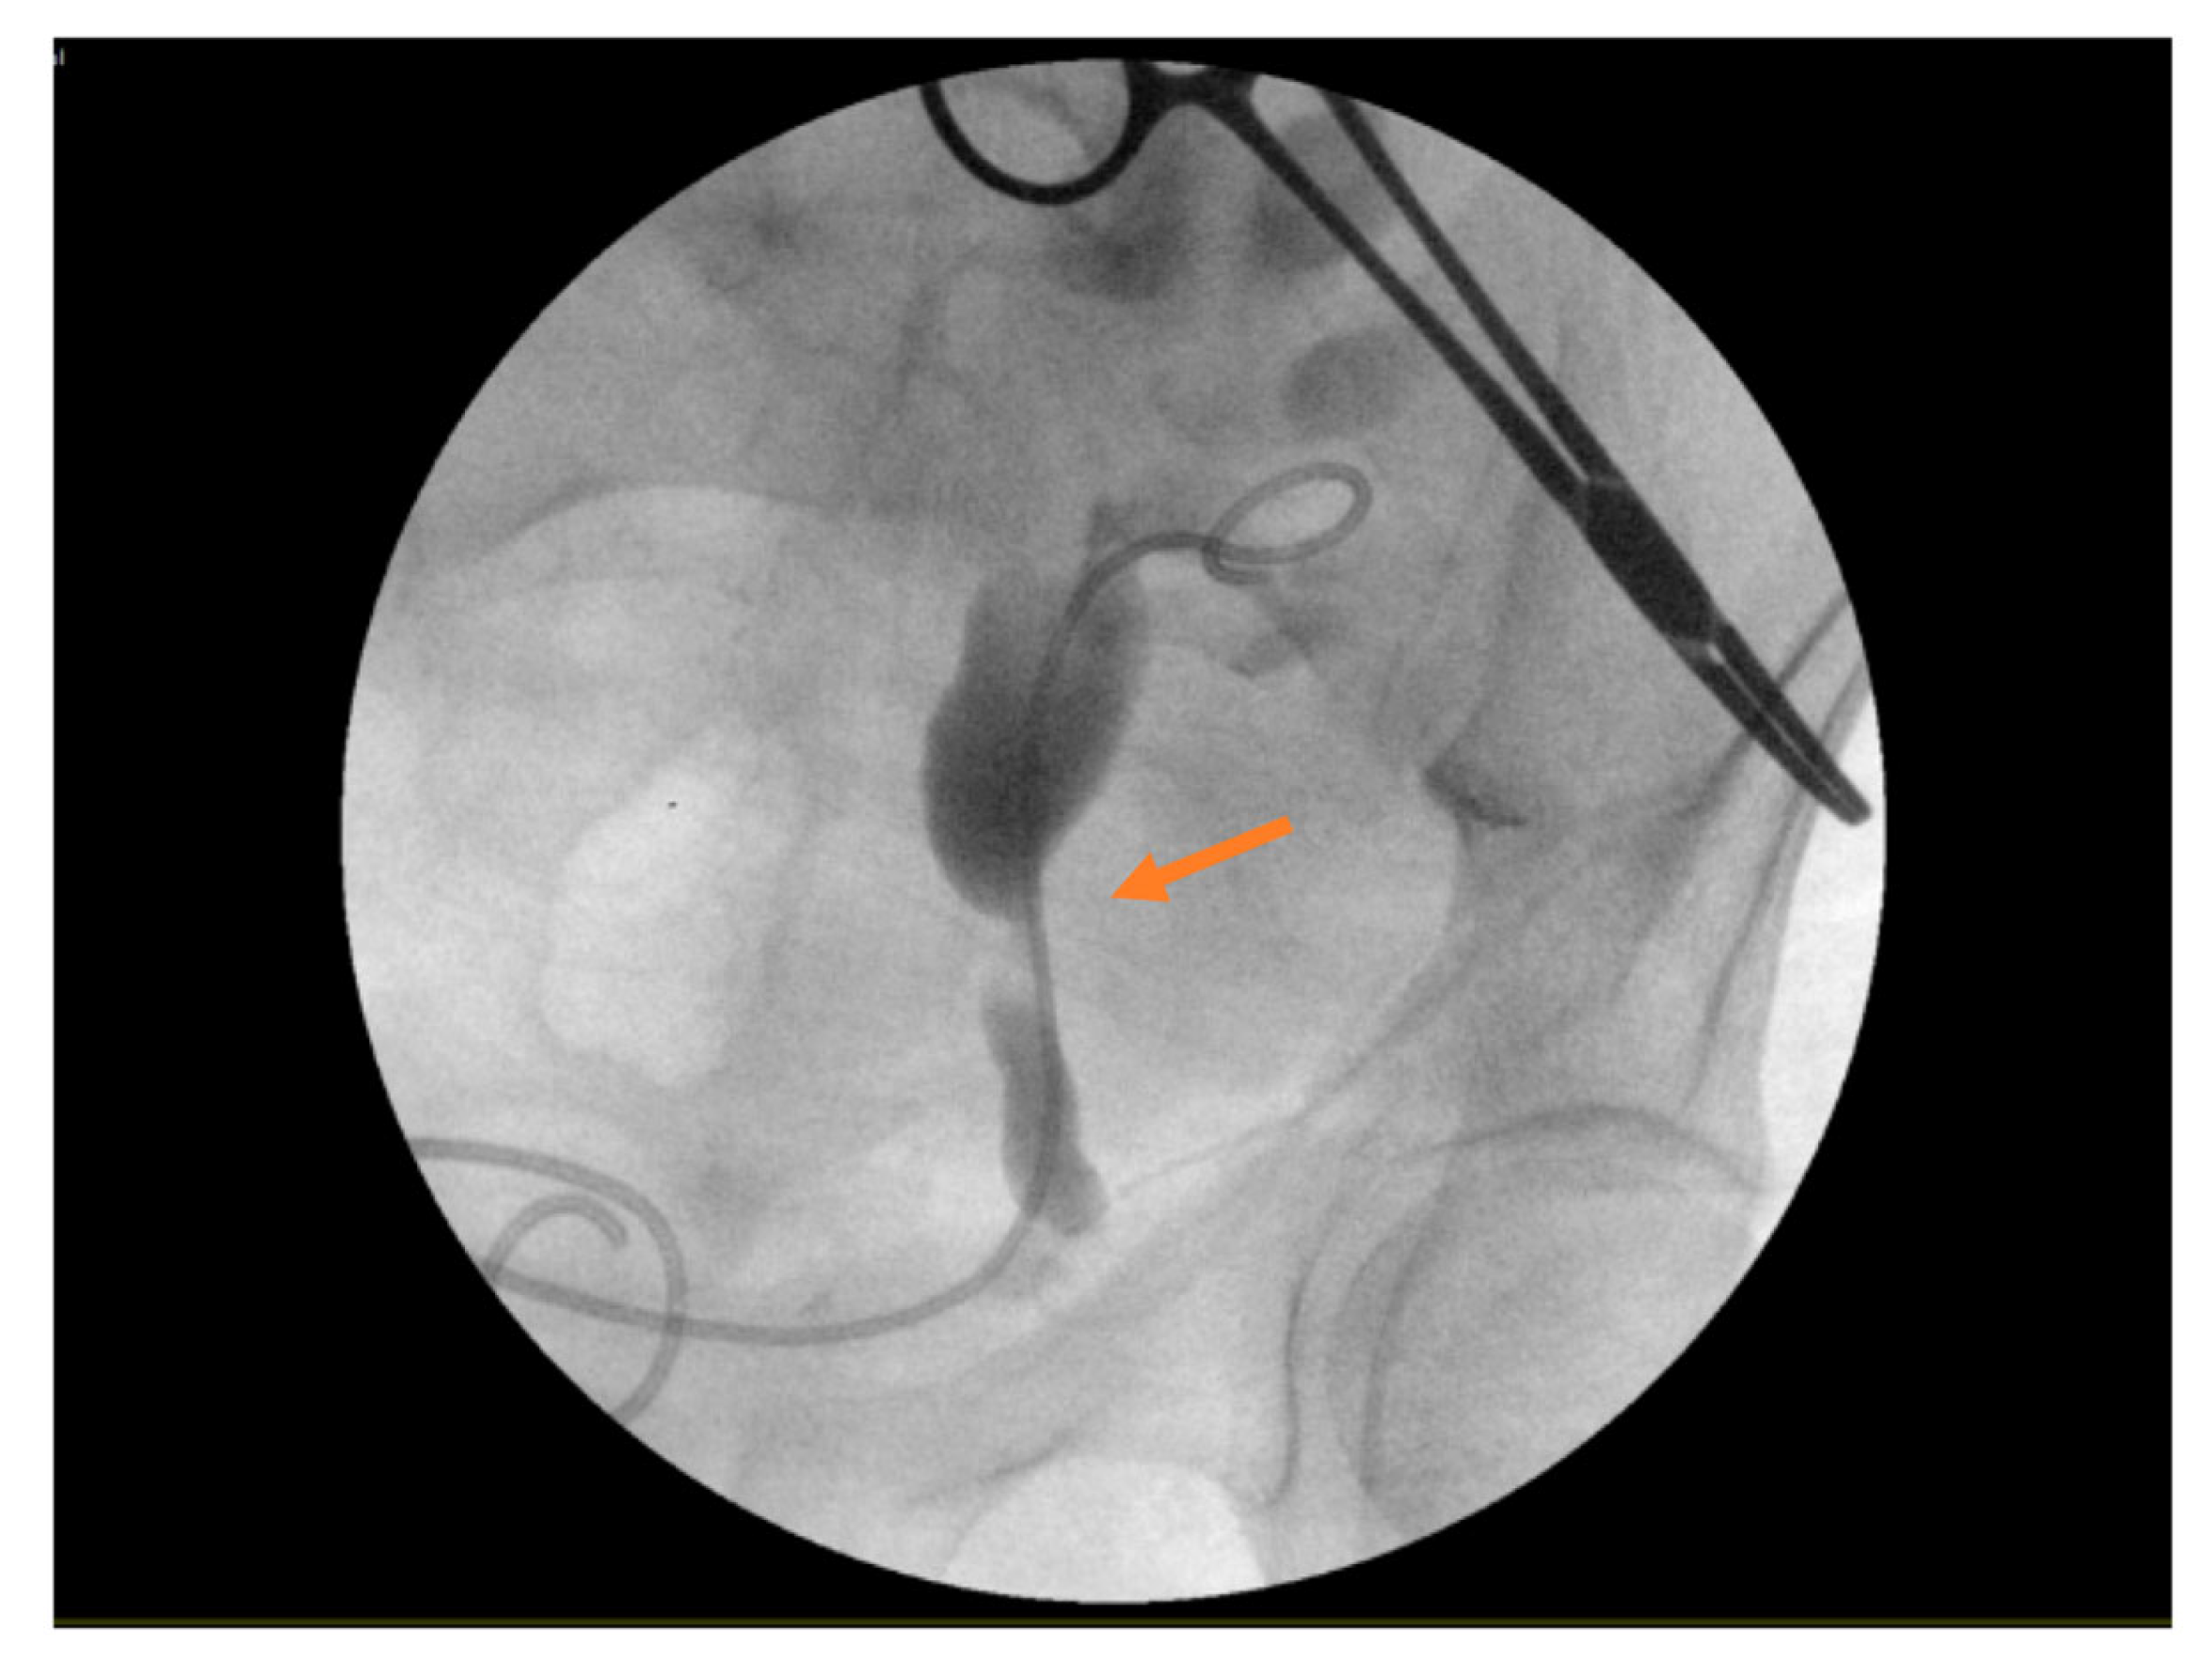

3.1. Case Report